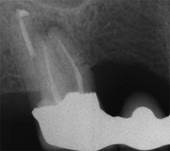

Das Ausgangsröntgenbild zeigt eine chronische Entzündung bei einer Wurzel. Die Brücke auf diesem Zahn ist noch intakt und muss nicht entfernt werden. Zur Rettung dieser Brücke kann die Wurzelspitze mit der Entzündung selektiv entfernt werden. -

Durch eine kleines Knochenfenster wird der entzündliche Anteil entfernt und die Wurzelspitze dicht verschlossen. -

Ein Jahr nach der Operation präsentieren sich gesunde Verhältnisse. Die Brücke konnte belassen werden.